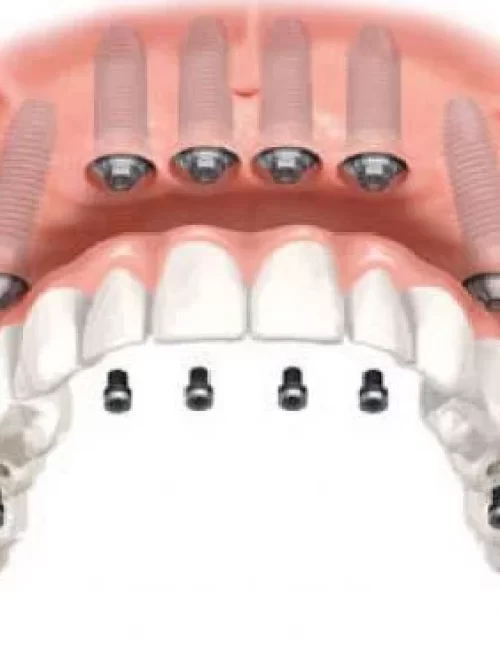

Protesi fisse su impianti

Le protesi fisse su impianti possono essere sostenute da un minimo di 4 impianti ad un massimo di 10 / 12 impianti con una struttura metallica di rinforzo.

Caratteristiche dell’implantologia All on 4

Protesi fissa su 4 impianti comprende una intera arcata dentale con una flangia di gengiva (overdentura), ed è una delle alternative più veloci ed economiche per avere di nuovo denti fissi anzichè una dentiera mobile.

Caratteristiche dell’implantologia All on 6

Protesi fissa su 6 impianti consiste nell’applicazione di una protesi di 12-14 denti, sorretta da 6 impianti. All on 6 è la tecnica piu innovativa dell’implantologia per ricostruire un’intera arcata con dei denti fissi.

Caratteristiche dell’implantologia All on 8

Protesi fissa su 8 impianti comprende una arcata circolare su impianti. Adatta per i pazienti affetti da mancanza totale dei denti per arcata, che ricercano la serenità di riacquisire un sorriso e una bocca perfettamente naturale.